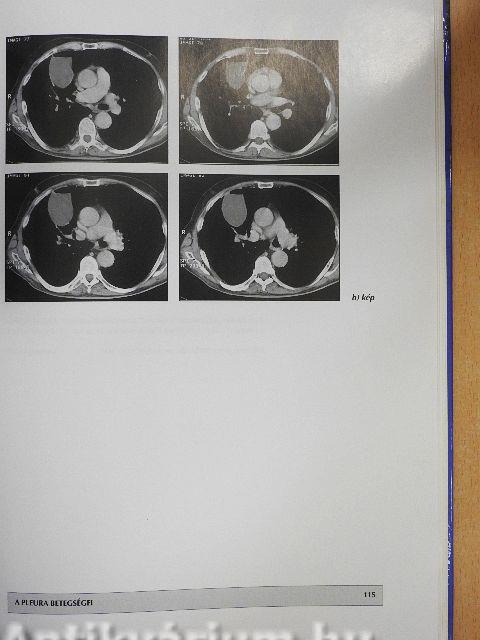

A pleura betegségei113